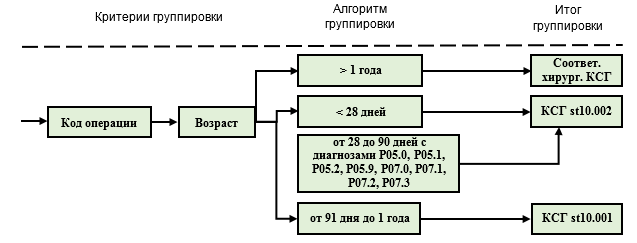

1-й аспект применения: диапазоны 1-3 используются для классификации случаев в КСГ st10.001 "Детская хирургия (уровень 1)", КСГ st10.002 "Детская хирургия (уровень 2)" и st17.003 "Лечение новорожденных с тяжелой патологией с применением аппаратных методов поддержки или замещения витальных функций":

- при возрасте ребенка до 28 дней (код 1) случаи классифицируются в КСГ st10.002 или st17.003 по соответствующему коду номенклатуры, независимо от кода диагноза.

- если ребенок родился маловесным, то по тем же кодам номенклатуры случай классифицируется в КСГ st10.002 или st17.003 при возрасте до 90 дней (код 2). При этом, признаком маловесности служит соответствующий код МКБ 10 (P05-P07), который используется как дополнительный диагноз (Код по МКБ 10 (2). В столбце "основной диагноз" может быть указан любой диагноз, который является основным поводом для госпитализации и проведения соответствующего хирургического вмешательства.

- при возрасте от 91 дня до 1 года (код 3), независимо от диагноза, случай классифицируется в КСГ st10.001 по коду номенклатуры.

Также код возраста 1 в сочетании с определенными диагнозами МКБ 10 применяется для отнесения случаев лечения к КСГ st17.005 "Другие нарушения, возникшие в перинатальном периоде (уровень 1)", КСГ st17.006 "Другие нарушения, возникшие в перинатальном периоде (уровень 2)" и КСГ st17.007 "Другие нарушения, возникшие в перинатальном периоде (уровень 3)". Например, диагноз J20.6 "Острый бронхит, вызванный риновирусом" при отсутствии дополнительного кода возраста 1 (дети до 28 дней) относится к КСГ st27.010 "Бронхит необструктивный, симптомы и признаки, относящиеся к органам дыхания", при наличии кода 1 - к КСГ st17.007 "Другие нарушения, возникшие в перинатальном периоде (уровень 3)".